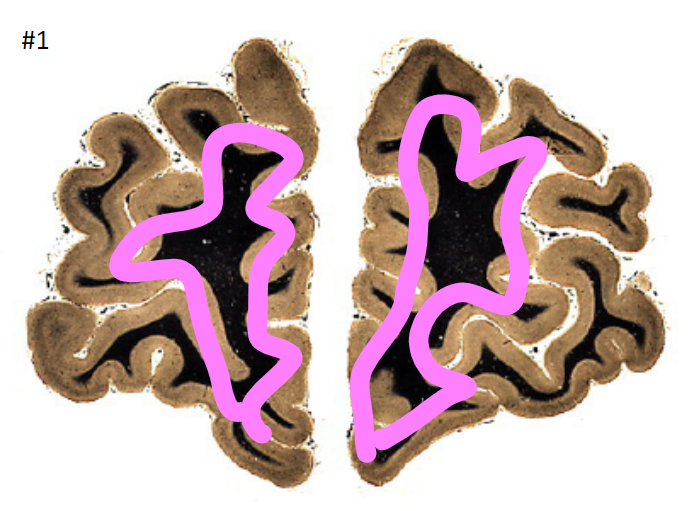

1

Q

what is the circled area (#1)?

A

the cortex

2

White matter